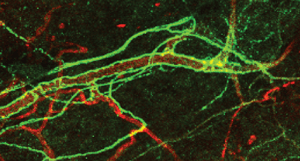

Thus, the brain controls the behaviour of blood stem cells through the innervation of MSC by sympathetic nervous system (SNS) fibres, and results in the control of haematopoiesis via release of norepinephrine (Fig. 1b). Dr David Scadden of the Harvard Stem Cell Institute in Boston, US, recently demonstrated that MSC-derived pivotal molecular drivers enforce the generation of lymphocytes, which are key cells participating in the generation of the adaptive immune repertoire through the interaction of specific MSC populations with haematopoietic stem or lineage-committed blood progenitor cells.

In a project funded by the Cariplo Foundation (N. 2015 – 1057), Italy, we are currently connecting these dots in the attempt to demonstrate that inflammatory cues sensed by the injured brain lead to the activation of neural sympathetic fibres which, in turn, signal to MSC in the BM. SNS-driven molecular changes in discrete MSC populations drive haematopoiesis and the release in the blood stream of lineage-committed cells, which contribute to modelling specific immune repertoires, possibly relevant for disease pathogenesis.